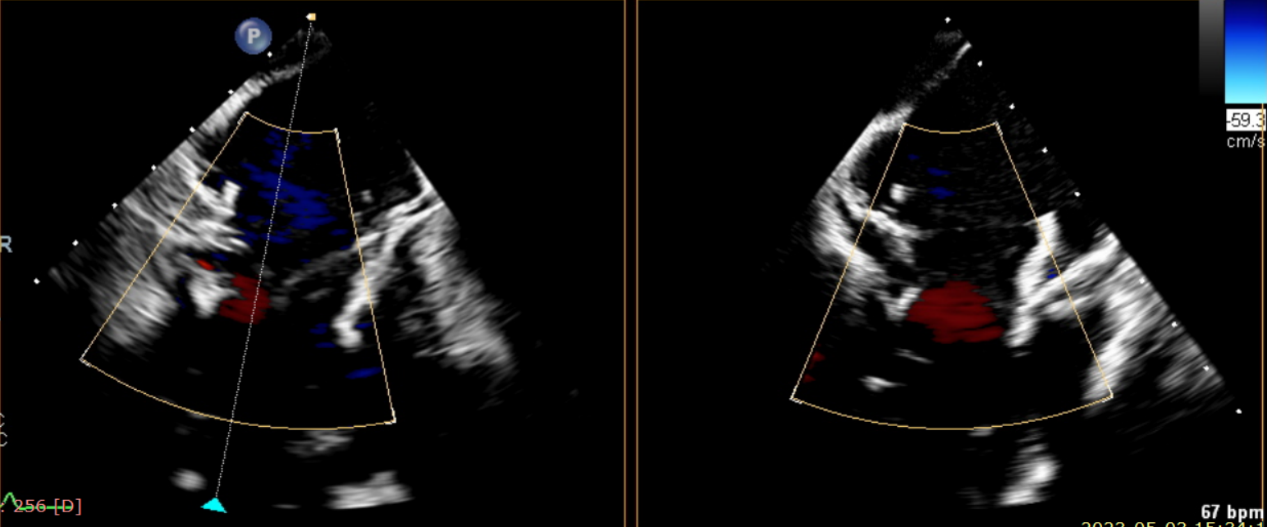

近日,美國紐約Montefiore醫學中心(Montrefiore Medical Center)的Azeem Latib教授團隊成功應用LuX-Valve Plus經血管三尖瓣置換系統為兩位三尖瓣大量反流的患者完成三尖瓣置換手術。術后超聲顯示人工三尖瓣植入穩定,瓣葉啟閉良好,僅殘余微量瓣周漏。患者于手術室即刻拔除氣管插管,血流動力學改善顯著。此次手術是LuX-Valve Plus于紐約的首次臨床應用,治療效果優異。

術后Azeem Latib教授對LuX-Valve Plus經血管三尖瓣置換系統的器械性能和治療效果大為稱贊,并且認為LuX-Valve Plus的手術體驗非常好。從治療效果來看,術后即刻超聲顯示三尖瓣反流幾乎完全消失,血流動力學改善顯著,患者恢復快。在面對復雜解剖結構、超聲影像質量不佳、有起搏導線干擾時,Lux-Valve Plus也體現了極強的適應性。Thomas Modine教授參與了術中指導,他同樣再次肯定了LuX-Valve Plus術中操作的便捷性,認為LuX-Valve Plus容錯率高,對術中影像的依賴小,并表達了后期希望可以更多地應用LuX-Valve Plus三尖瓣置換系統于臨床實踐,讓更多的三尖瓣重度反流患者盡早獲益,改善預后。